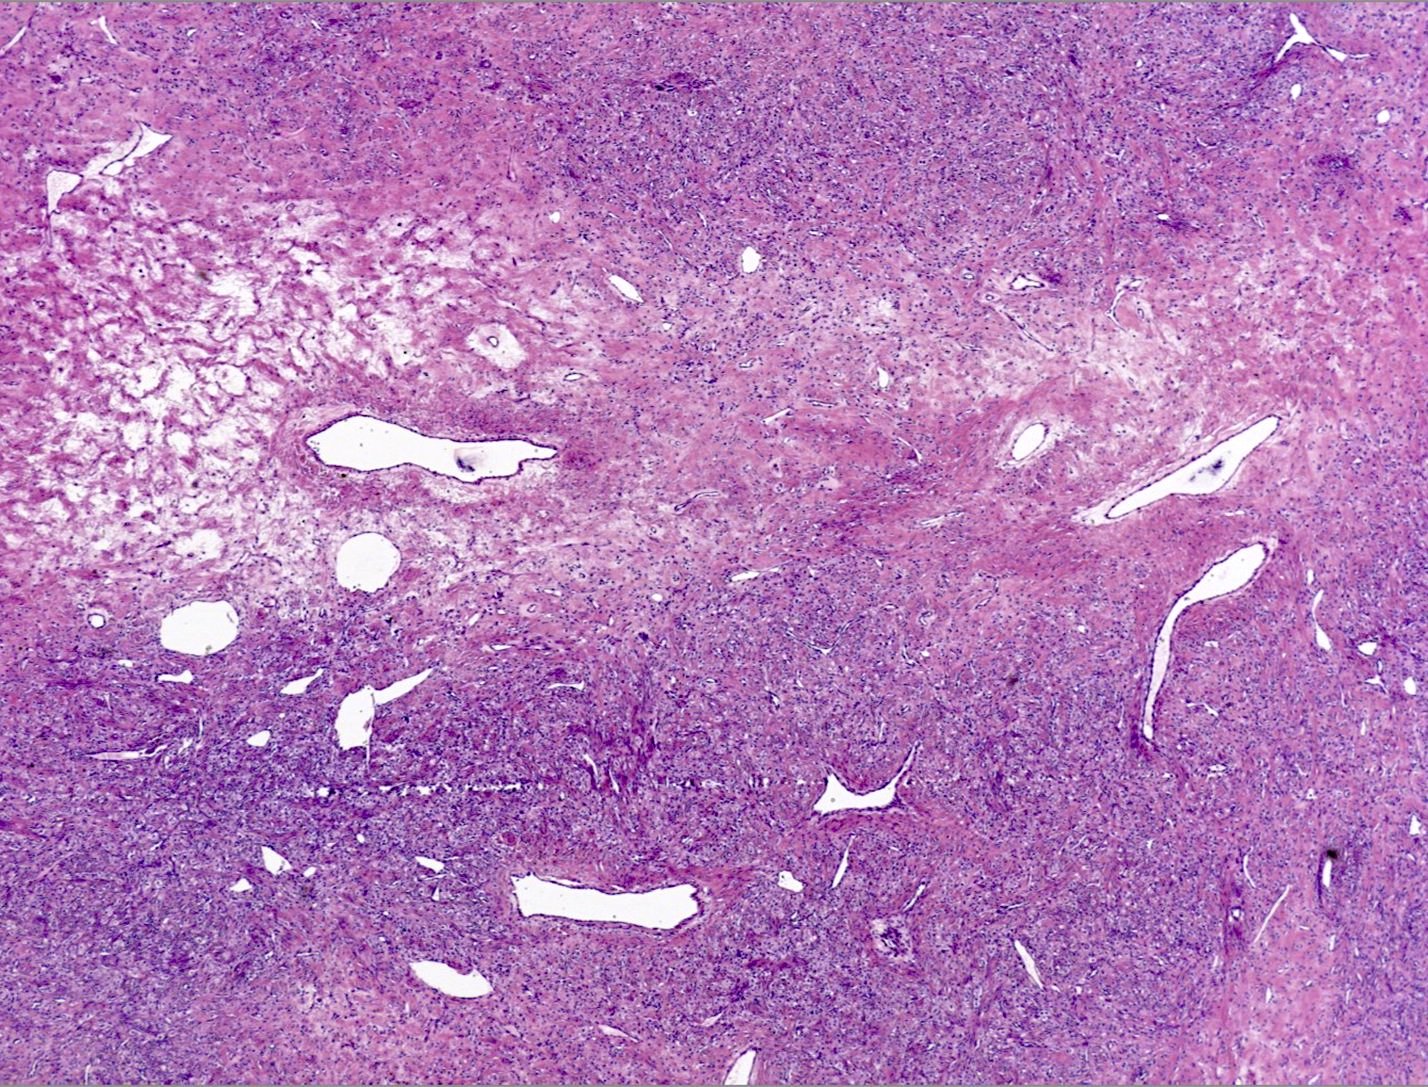

Microscopic (histologic) description

- Alternating cellular and hypocellular areas impart a pseudolobular appearance

- Hypocellular foci may be ill defined in pregnancy due to expansion of the pseudolobules by lutein cells (Int J Gynecol Pathol 2015;34:357)

- Thin, dilated and branching hemangiopericytoma-like vasculature is often conspicuous in both components

- Pseudolobules comprised of a jumbled admixture of epithelioid (lutein) and spindled cells with minimal atypia

- Epithelioid cells: round nuclei with prominent nucleoli, vesicular chromatin and clear to vacuolated cytoplasm

- Abundant eosinophilic cytoplasm often seen in pregnancy (Int J Gynecol Pathol 2015;34:357)

- Occasionally have a signet ring-like appearance

- Spindled cells: elongated nuclei with indistinct nucleoli, bland chromatin and scant eosinophilic cytoplasm

- Typically round to ovoid but may show angulation if edema is striking

- Epithelioid cells: round nuclei with prominent nucleoli, vesicular chromatin and clear to vacuolated cytoplasm

- Hypocellular areas can be edematous, collagenous (variably keloid-like) or myxoid

- Mitoses are often inconspicuous but rarely can be up to 12/10 high power fields, no atypical forms (Int J Gynecol Pathol 2016;35:549)

- Infarct type necrosis and calcification infrequent

- References: Cancer 1973;31:664, Histopathology 2022;80:360

Microscopic (histologic) images